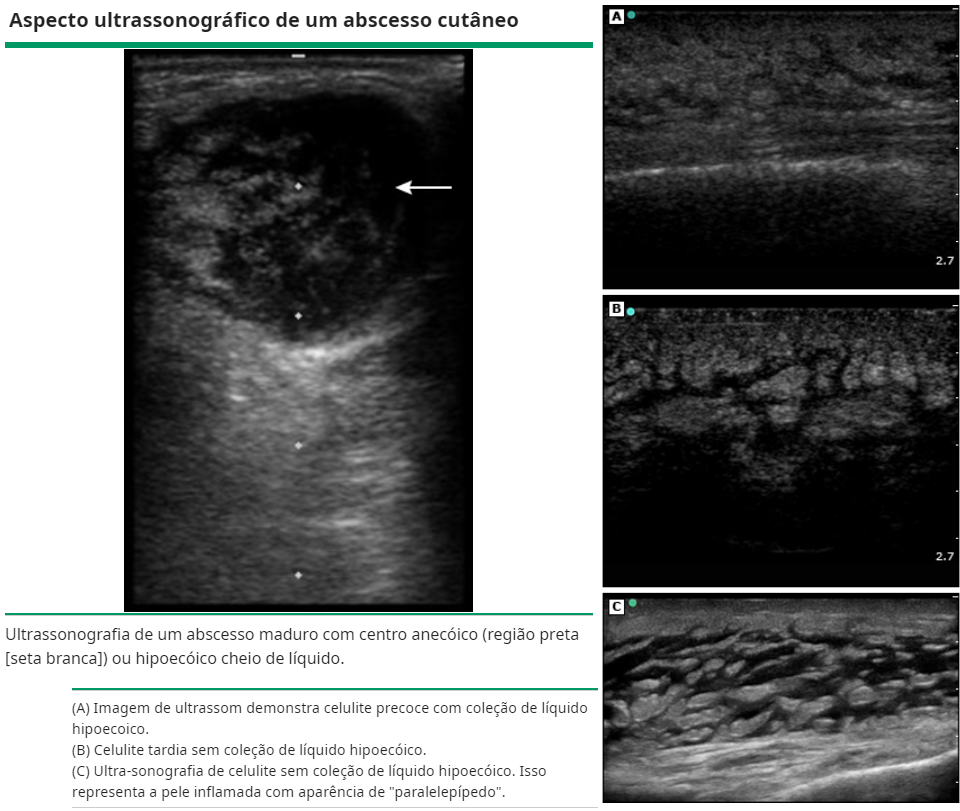

Qual exame pode auxiliar no dx e drenagem do abcesso cutâneo?

A USG a beira leito.

Quais os achados do abcesso na USG?

.